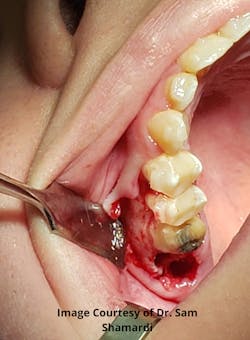

Patient procedure completed: Extraction of residual root tips from fracture of tooth no. 2 and crown lengthening for no. 3.

A dental crown lengthening procedure adjusts the gum and bone level to expose more of the tooth so it can be restored.

Crown lengthening is advised in this specific case because the decay was so large that the natural tooth structure left behind is not the recommended amount to properly hold the crown. At least 3 to 4 mm of sound root structure must be exposed below the most apical extent of the proposed restoration. Crown lengthening can also be used to remove excess gingiva for "gummy" smiles or provide better esthetics, especially around anterior veneers or crowns.